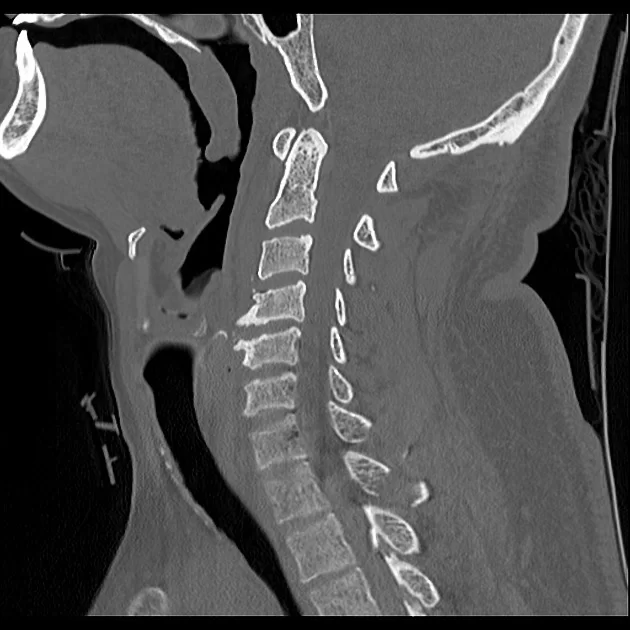

Η διάγνωση μπαίνει με τον ίδιο τρόπο που διαγιγνώσκονται οι περισσότερες παθήσεις της σπονδυλικής στήλης. Μετά το λεπτομερές ιστορικό και την κλινική εξέταση ο γιατρός θα ζητήσει κάποιες απεικονιστικές εξετάσεις όπως είναι οι ακτινογραφίες και η αξονική ή η μαγνητική τομογραφία. Η πιο αποτελεσματική εξέταση για να αναδείξει την έκταση των οστεοφύτων είναι η αξονική τομογραφία.